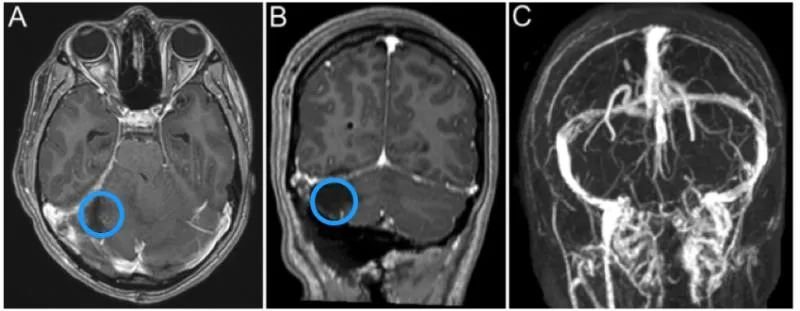

孩子病情耽误不得!父母立刻带着Anita来到加拿大多伦多大学Sickkids医院。核磁扫描结果显示,Anita右侧小脑半球存在 5.6×5.0×3.4 cm的高信号巨大占位,且肿瘤已经压迫第四脑室,伴发梗阻性脑积水。

术后MRI显示Anita的右侧横窦内小脑实质部分全部切除,有少量强化肿瘤(< 1.5c㎡)。术后临床检查显示脑神经正常,无明显运动或感觉功能障碍,轻度舒张功能障碍,轻度躯干共济失调,术后半年症状明显好转。随访 8 年,孩子无神经功能缺损,无肿瘤复发。一次手术,让Anita父母不再提心吊胆,而孩子的未来也缓慢展开……